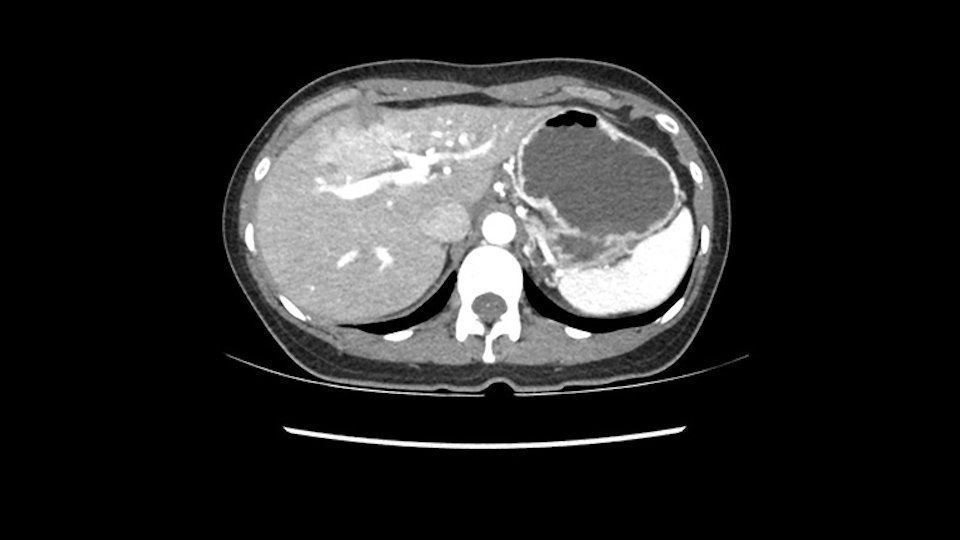

So if we look at the CT scan, on the axial, it’s a larger lesion. It’s about 6 or 7 or 8 centimeters. So it does look a bit threatening in terms of its resectability but if you really drill down deeply into the anatomy, and I think the coronal [imaging] is even better, you can see that the entire mass is on the patient’s left side of the falciform ligament. So it’s really only a left-sided tumor and not even really a left-sided tumor because Segment 4 is uninvolved anatomically.

As I review the CT scan, we have both arterial and venous phases, the tumor is obvious. But I’ll start by saying that the liver itself does not appear to be cirrhotic to my eye. It’s got a normal contour and allied to that, that I do not see evidence of portal hypertension. The spleen is normal, there’s no collateral vessels. The tumor itself, I measured maximally at about 11 centimetres in diameter and I’m told the alpha fetoprotein is very high (over 10000), which is entirely consistent with this being a solitary hepatocellular carcinoma that is very exophytic. It seems to emanate off the inferior margin of Segment 3 (because that’s the falciform). I’ll start by saying that this is not transplantable. The tumor exceeds our guidelines for transplantation, but it's likely resectable based on normal liver and no portal hypertension.

When you see the axial sections of the scan, you find it's a largely exophytic mass and its well-encapsulated. So this is typically true of a well-differentiated hepatocellular carcinoma. If you look at this, this is the gallbladder which is being displaced to the right and the mass is in the Sg4 of the liver, exophytic, projecting down. As it is coming down, it is also displacing the duodenum and the head of the pancreas which is being pushed towards the left and it's going right up to the cava, the start of the anterior surface of the cava. Obviously getting a lot of collaterals and vascularity from all the vessels around but one has to be very careful in evaluation of the main portal pedicle in this particular case and of course arterial inflow to the Sg4 and of course the left lobe of the liver.